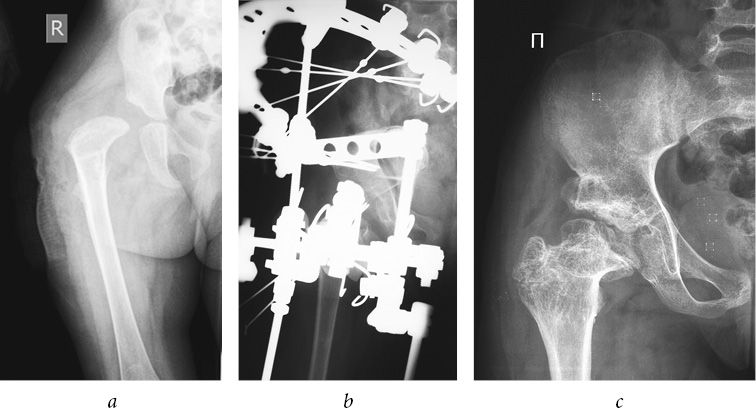

Fig. 3. Patient F., 4 years old, with a diagnosis of congenital dislocation of the right hip, degree III of dislocation, and degree IV Perthes disease: a — frontal radiograph of the hip joint before treatment; b — frontal radiograph of the hip joint during treatment (after performing an open reduction of the dislocation, shortening correcting osteotomy of the hip, osteotomy of the iliac bone, tunneling of the femoral neck and head, hardware decompression of the articulation); c — frontal radiograph of the hip joint 4 years after treatment